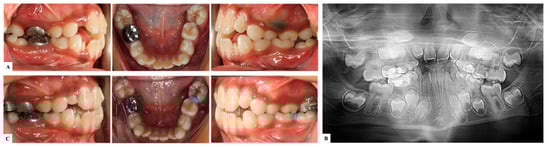

9.1. Interproximal Wedging